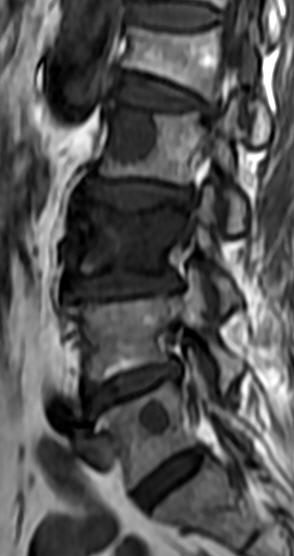

MRI

可提供腰椎管的矢状面、冠状面和轴位横断面上的影像。椎管狭窄以T2加权像显示较好,脑脊液为高信号,产生所谓“脊髓造影”的效果,而骨质增生,骨赘、间盘均为低信号,能清晰地显示椎管狭窄,以及对脊髓的压迫情况。但对肥大的黄韧带、骨质增生等的判断则不如较高清晰度CT扫描。

腰椎正常MRI解剖。

腰椎管狭窄MRI表现。